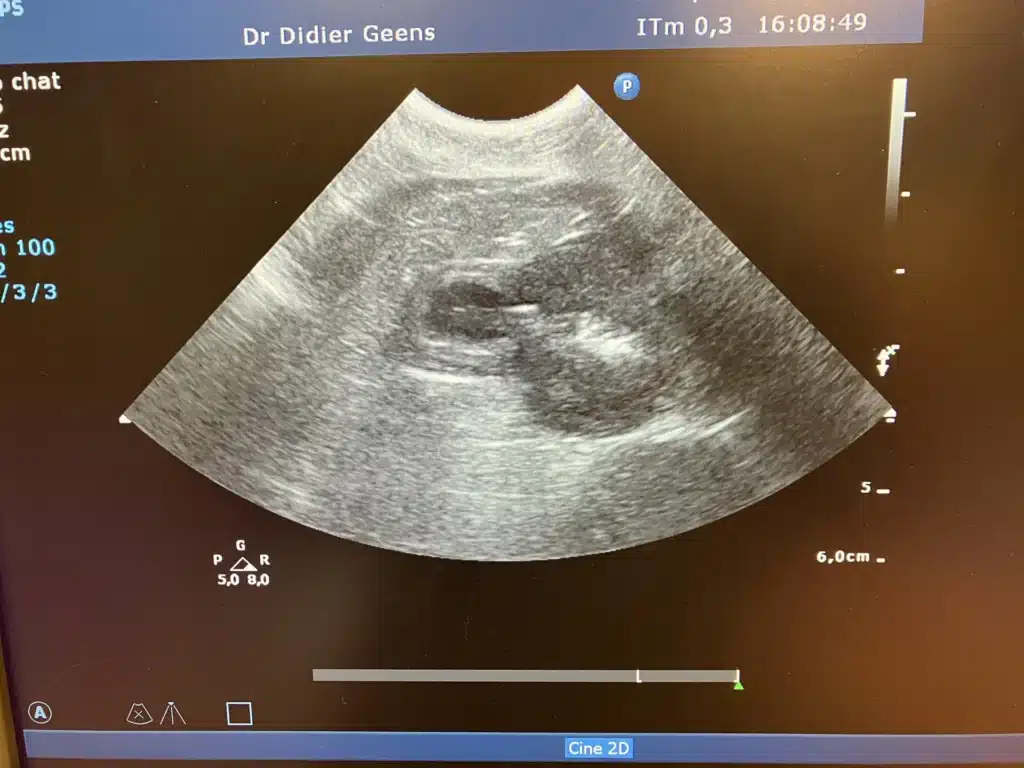

Un chat de 13 ans est venu pour vomissements. Comme il est maigre et qu'il boit un peu plus, j'ai proposé une échographie. Le rein a une apparence anormale, il est hyperéchogène, ce qui fait penser à une néphrite. Une prise de sang effectuée a permis de confirmer une insuffisance et une infection rénales , un traitement a pu être instauré le soir même.